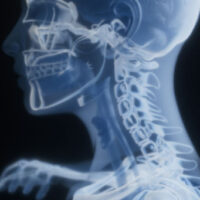

Cervical Spine Fractures After a Car Accident: Severe Neck Injuries and Legal Help

Cervical spine fractures are among the most dangerous car accident injuries because they involve the delicate vertebrae in the neck that protect the spinal cord. Even a single fracture in the cervical spine can lead to paralysis, respiratory complications, or death. Car accidents across Virginia, Maryland, and Washington, DC are a leading cause of… Read More »